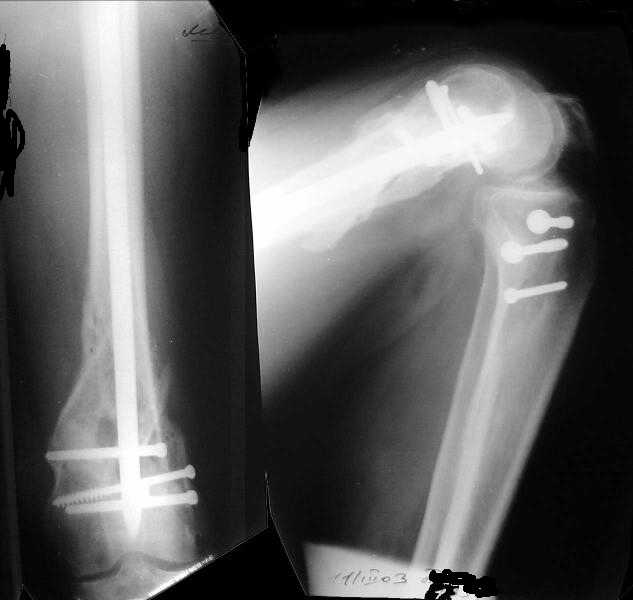

1

2

de> you think you are using antigrade nails for some very low

de> fractures including some intercondylar fractures.

Exactly. It seems the option looks underestimated.

de> Do ou have a reference supporting antigrade nailing in such

de> occasio in favour of other choices eg DCS, Supracondylar nail,

No, i haven't seen such comparisons. However some advantages of closed antegrade nailing vs conventional plating looks self-evident like no site opeining, no bone skeletization, less blood loss, no need for autografting... If you or other colleagues can help me with the references it would be greatly appreciated. I would be interested also to compare ante- vs retrograde nailing for the localization.

de> And perhaps you could show us also some of your results ,

de> that is (follow up) not immediate postop x rays.

I attached an example of C2 fracture with result of the same technique in 5 months.

[ Ответить ]